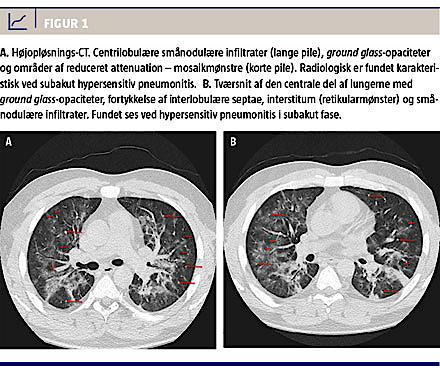

Der blev udført højopløsnings-CT af thorax, og man fandt ILS af typen hypersensitive pneumonitis (Figur 1). Der blev iværksat højdosis-CS-behandling og foretaget undersøgelse for antinukleært antistof, glomerulær basalmembranantistof, antineutrofilocytcytoplasmaantistoffer, hiv, tuberkulosequantiferontest, og af ekspektorat fra en trakealsugning, hvor man undersøgte for tuberkulose, cytomegalovirus og pneumocyster – alle test var negative.

A 41-year-old man developed severe interstitial lung disease (ILD) after treatment with infliximab (IFX) and azathioprine (AZA). A relapse of ulcerative colitis was treated with corticosteroids (CS) and IFX as rescue therapy. Following remission AZA was given as prophylaxis. AZA was initiated the same day as the third infusion of IFX (week 6). Within a few days he developed signs of lung involvement progressing into severe ILD. A high resolution computed tomography showed subacute hypersensitive pneumonitis. He was treated with oxygen and high dose CS. After three months his state of health had returned to normal.